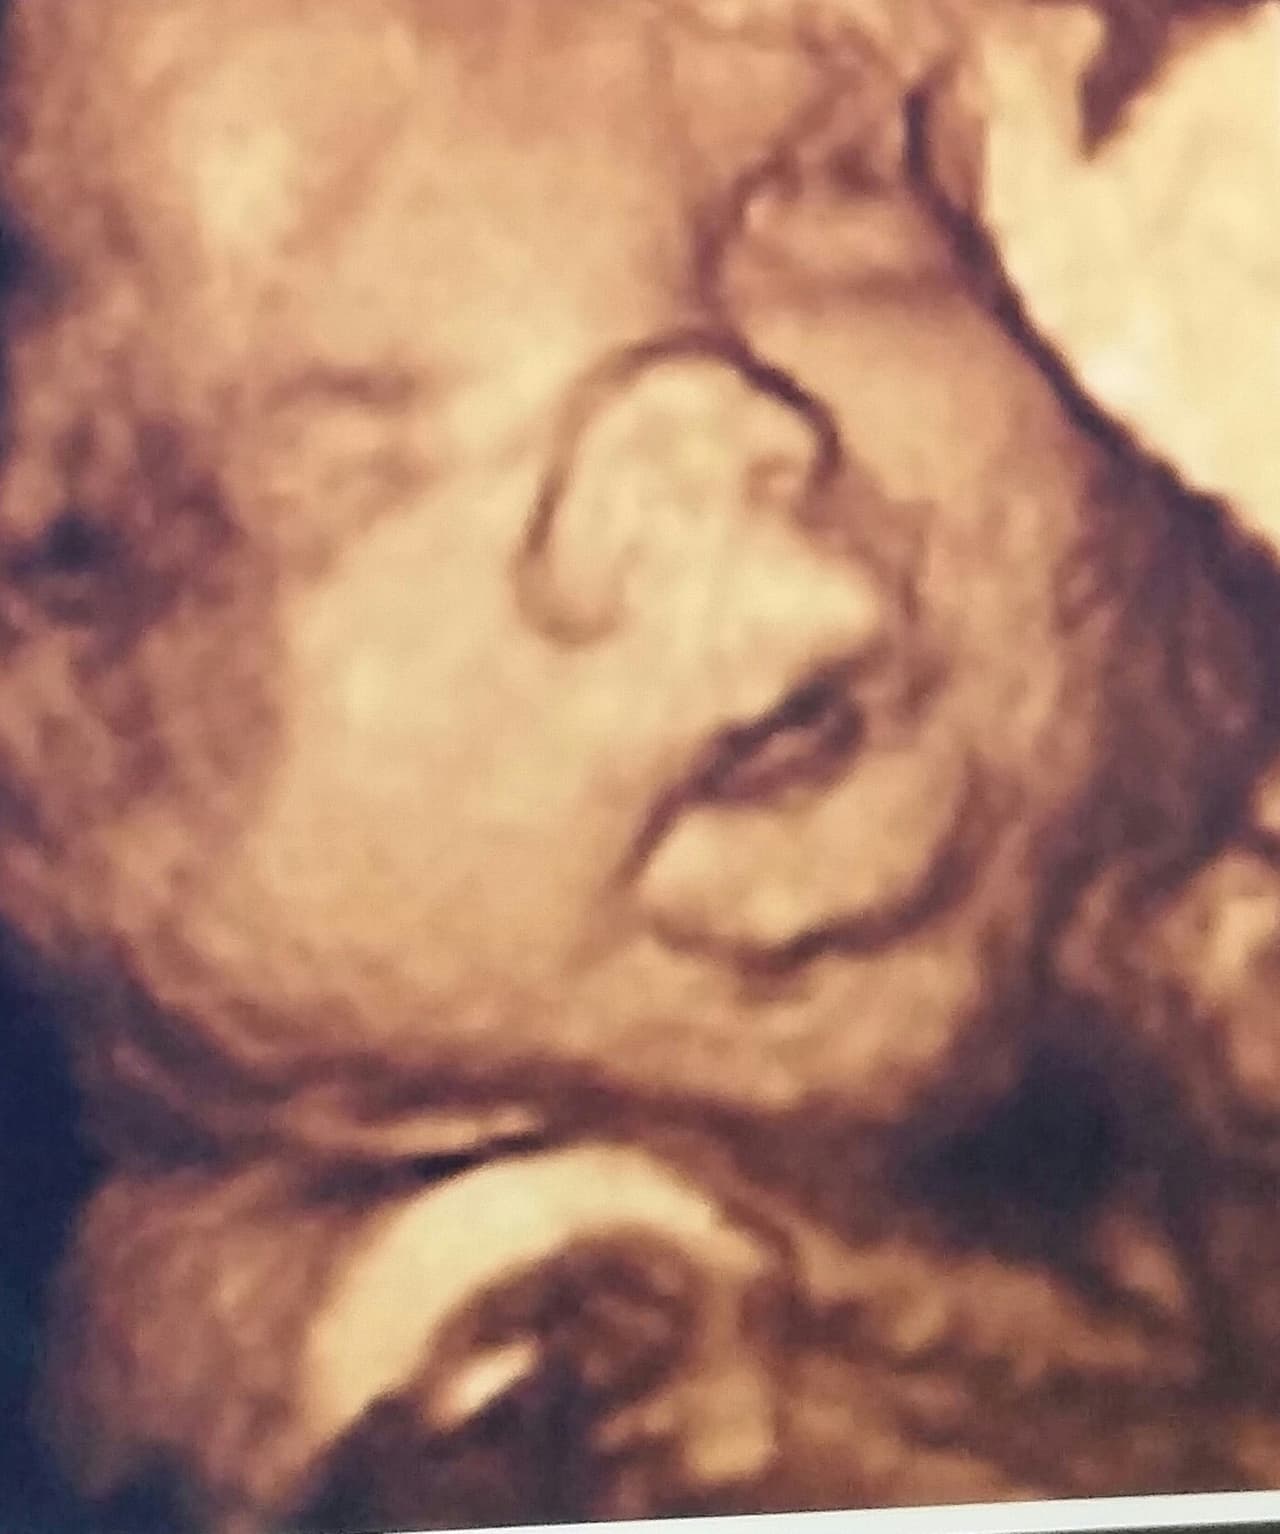

La presentadora se goza su maternidad al máximo y nos compartió su sonograma 4D.

Gredmarie, quien a sus 15 semanas de gestación, dio a conocer el sexo de su bebé durante la transmisión en vivo de Rubén & Co, vive encantada de tener una niña y por eso compartió con sus seguidores en Rubén & Co. la experiencia de ver a su bebé en un sonograma 4D.